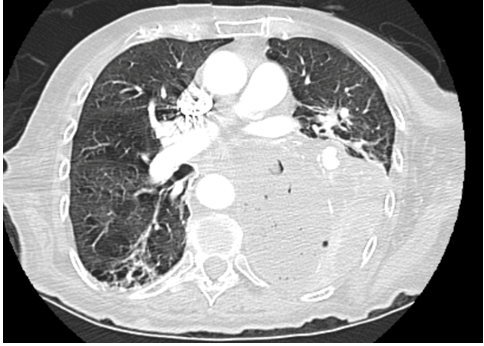

Within one month of discharge, patient returned to the emergency department with worsening cough, shortness of breath, hemoptysis and performance status. The patient received 65% of planned radiation treatments prior to arrival. Computed tomography scan of the chest revealed a 14x9x6 cm large mass like structure in the left lower lobe containing complex fluid and multiple pockets of air suggestive of an infected or necrotic tumor (Figure 3) (Figure 4) (Figure 5). Based on the progression and aggressiveness of the tumor, the patient decided to go on hospice. Shortly after, the patient died from respiratory failure.

Figure 4: Computed tomography scan of chest showing large mass like structure in the left lower lobe containing complex fluid and multiple pockets of air suggestive of an infected or necrotic tumor.

Figure 5: Computed tomography scan of chest showing a 14x9x6 cm large mass like structure in the left lower lobe containing complex fluid and multiple pockets of air suggestive of an infected or necrotic tumor..